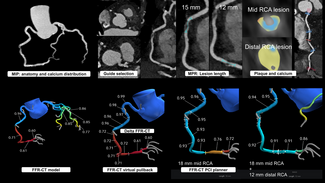

A 59-year-old man was referred to our institution for potential MitraClip (Abbott Vascular) therapy after he was found to have severe mitral regurgitation (MR) seen on transthoracic echocardiography. He had a history of coronary artery disease and functional MR, and underwent coronary artery bypass grafting and mitral annuloplasty (28 mm CG Future; Medtronic Inc.) 4 years prior at an outside institution. A permanent pacemaker was also implanted for advanced atrioventricular block. The procedure was complicated by a methicillin-resistant  staph aureus sternal wound infection requiring multiple debridements and wound vacuum drainage for 1 year. There was no documented bacteremia at that time. Three years later, he had several admissions for decompensated heart failure, volume overload, and pulmonary edema without angina pectoris. Transthoracic echocardiogram revealed left ventricular (LV) ejection fraction of 55%, severe MR with 2 distinct regurgitant jets, and an estimated right ventricular pulmonary systolic pressure of 60 mm Hg. Subsequent transesophageal echocardiography (TEE) demonstrated a dilated mitral annulus with the septal-lateral dimension measuring 36 mm. There was significant dehiscence of the annuloplasty ring from the posterior annulus and focal dehiscence at the right fibrous trigone, with a resultant 6 x 8 mm perforation at the base of the anterior mitral leaflet (Figure 1). There was 4+ MR through the mitral leaflet perforation and 1+ central MR. There was trivial regurgitation through the posterior dehiscence (Figure 2). After referral to our center, 3.5 years after the original operation, several blood cultures drawn on different days were negative and an erythrocyte sedimentation rate was normal. Angiography demonstrated occluded vein grafts to the left circumflex and right coronary arteries with severe native diffuse disease not amenable to percutaneous or surgical revascularization. The left internal mammary artery graft to left anterior descending artery was patent. In view of his related comorbidities and prior sternal wound infection, percutaneous repair of the anterior mitral leaflet perforation was performed.

staph aureus sternal wound infection requiring multiple debridements and wound vacuum drainage for 1 year. There was no documented bacteremia at that time. Three years later, he had several admissions for decompensated heart failure, volume overload, and pulmonary edema without angina pectoris. Transthoracic echocardiogram revealed left ventricular (LV) ejection fraction of 55%, severe MR with 2 distinct regurgitant jets, and an estimated right ventricular pulmonary systolic pressure of 60 mm Hg. Subsequent transesophageal echocardiography (TEE) demonstrated a dilated mitral annulus with the septal-lateral dimension measuring 36 mm. There was significant dehiscence of the annuloplasty ring from the posterior annulus and focal dehiscence at the right fibrous trigone, with a resultant 6 x 8 mm perforation at the base of the anterior mitral leaflet (Figure 1). There was 4+ MR through the mitral leaflet perforation and 1+ central MR. There was trivial regurgitation through the posterior dehiscence (Figure 2). After referral to our center, 3.5 years after the original operation, several blood cultures drawn on different days were negative and an erythrocyte sedimentation rate was normal. Angiography demonstrated occluded vein grafts to the left circumflex and right coronary arteries with severe native diffuse disease not amenable to percutaneous or surgical revascularization. The left internal mammary artery graft to left anterior descending artery was patent. In view of his related comorbidities and prior sternal wound infection, percutaneous repair of the anterior mitral leaflet perforation was performed.

The procedure was performed under general anesthesia with three-dimensional TEE guidance, and periprocedural prophylactic antibiotics were given. The anterior mitral leaflet perforation measured 6 x 8 mm (area, 0.37 cm2), and the anterior mitral leaflet length was measured at 22 mm. As the left atrial (left ventricular, for this case) disc for a 5 mm Amplatzer septal occluder (St. Jude Medical) was 17 mm, it was felt that the device would not restrict the motion of the leaflet and still adequately seal the perforation.

The procedure was performed under general anesthesia with three-dimensional TEE guidance, and periprocedural prophylactic antibiotics were given. The anterior mitral leaflet perforation measured 6 x 8 mm (area, 0.37 cm2), and the anterior mitral leaflet length was measured at 22 mm. As the left atrial (left ventricular, for this case) disc for a 5 mm Amplatzer septal occluder (St. Jude Medical) was 17 mm, it was felt that the device would not restrict the motion of the leaflet and still adequately seal the perforation.

Initially, right heart catheterization was performed that demonstrated pulmonary arterial pressure of 40/20 with mean pulmonary capillary wedge pressure of 18 mm Hg and V waves up to 22 mm Hg. Simultaneously, left heart catheterization revealed LV end diastolic pressure of 17 mm Hg, ruling out mitral stenosis. A BRK needle (St. Jude Medical) was used to perform transseptal puncture under echocardiographic guidance and a Mullins transseptal sheath (Medtronic Inc.) was advanced through the interatrial septum in a superior location within the fossa ovalis. Intravenous heparin was given at this point. Mean left atrial pressure was recorded at 18 mm Hg with prominent V waves up to 40 mm Hg. The Mullins sheath was then removed and a medium curl Agilis NxT catheter (11.5 Fr outer diameter, 8.5 Fr inner diameter, St. Jude Medical) was advanced into the left atrium and directed toward the base of the anterior mitral leaflet. Through the Agilis catheter, an 8 Fr EBU 3.75 guiding catheter (Medtronic Inc.) was then advanced to its tip. Another multipurpose catheter was then nested through the guiding catheter using a triple telescoping “mother and child” approach. An exchange-length 0.035˝ angled Glidewire (Terumo Medical Corporation) was then advanced through the leaflet perforation using three-dimensional TEE guidance in an antegrade fashion. Over the Glidewire, the multipurpose catheter was passed through the defect into the LV apex. The Glidewire was then exchanged for an Amplatz Superstiff wire (Boston Scientific), over which the EBU guiding catheter was advanced in the LV cavity (Figure 2). Once the guiding catheter was appropriately positioned in the LV midcavity, the multipurpose catheter as well as the stiff wire were removed. Then, a 5 mm Amplatzer atrial septal occluder was loaded into the guiding catheter and deployed successfully to the anterior mitral leaflet perforation under TEE guidance (Figure 3). On color Doppler, there was no residual MR through the leaflet perforation and only 1+ functional (central) MR with excellent device stability (Figures 1 and 4). The anterior mitral leaflet had preserved mobility and there was no obstruction of the LVOT (Figure 4). Mean left atrial pressure after the repair was 15 mm Hg with diminished V waves. Final transmitral gradient was 4 mm Hg with mitral valve area of 2.5 cm2. Procedural fluoroscopy time was 27 minutes. The postprocedure course was uneventful and the patient was discharged on aspirin and clopidogrel on postprocedure day 1. At 1-month follow-up, he was in New York Heart Association functional class I. He developed transient mild hemolytic anemia, which did not require transfusion. On follow-up echocardiogram, there was no residual MR through the defect and only 1+ central MR.

Initially, right heart catheterization was performed that demonstrated pulmonary arterial pressure of 40/20 with mean pulmonary capillary wedge pressure of 18 mm Hg and V waves up to 22 mm Hg. Simultaneously, left heart catheterization revealed LV end diastolic pressure of 17 mm Hg, ruling out mitral stenosis. A BRK needle (St. Jude Medical) was used to perform transseptal puncture under echocardiographic guidance and a Mullins transseptal sheath (Medtronic Inc.) was advanced through the interatrial septum in a superior location within the fossa ovalis. Intravenous heparin was given at this point. Mean left atrial pressure was recorded at 18 mm Hg with prominent V waves up to 40 mm Hg. The Mullins sheath was then removed and a medium curl Agilis NxT catheter (11.5 Fr outer diameter, 8.5 Fr inner diameter, St. Jude Medical) was advanced into the left atrium and directed toward the base of the anterior mitral leaflet. Through the Agilis catheter, an 8 Fr EBU 3.75 guiding catheter (Medtronic Inc.) was then advanced to its tip. Another multipurpose catheter was then nested through the guiding catheter using a triple telescoping “mother and child” approach. An exchange-length 0.035˝ angled Glidewire (Terumo Medical Corporation) was then advanced through the leaflet perforation using three-dimensional TEE guidance in an antegrade fashion. Over the Glidewire, the multipurpose catheter was passed through the defect into the LV apex. The Glidewire was then exchanged for an Amplatz Superstiff wire (Boston Scientific), over which the EBU guiding catheter was advanced in the LV cavity (Figure 2). Once the guiding catheter was appropriately positioned in the LV midcavity, the multipurpose catheter as well as the stiff wire were removed. Then, a 5 mm Amplatzer atrial septal occluder was loaded into the guiding catheter and deployed successfully to the anterior mitral leaflet perforation under TEE guidance (Figure 3). On color Doppler, there was no residual MR through the leaflet perforation and only 1+ functional (central) MR with excellent device stability (Figures 1 and 4). The anterior mitral leaflet had preserved mobility and there was no obstruction of the LVOT (Figure 4). Mean left atrial pressure after the repair was 15 mm Hg with diminished V waves. Final transmitral gradient was 4 mm Hg with mitral valve area of 2.5 cm2. Procedural fluoroscopy time was 27 minutes. The postprocedure course was uneventful and the patient was discharged on aspirin and clopidogrel on postprocedure day 1. At 1-month follow-up, he was in New York Heart Association functional class I. He developed transient mild hemolytic anemia, which did not require transfusion. On follow-up echocardiogram, there was no residual MR through the defect and only 1+ central MR.

For percutaneous leaflet repair, high-quality two-and three-dimensional TEE are essential to delineate defect dimensions and motion of the anterior mitral leaflet in relation to the left ventricular outflow tract (LVOT). We utilized real-time three-dimensional TEE of the mitral valve as well as fluoroscopy to direct the guiding catheter and deploy the device. A triple-telescoping catheter technique that has been previously described was used to cross the very medial and somewhat posterior defect.20 For device selection, it is important to consider the diameters of the waist and two retention discs. We chose an Amplatzer septal occluder due to the very low profile and small disc diameters, which minimized the potential of restricting leaflet motion or obstructing the LVOT. Although use of an Amplatzer vascular plug has been described for a mitral leaflet perforation as a complication of mechanical aortic valve replacement, this device has substantial height and may not be the ideal choice for patching a leaflet perforation.7